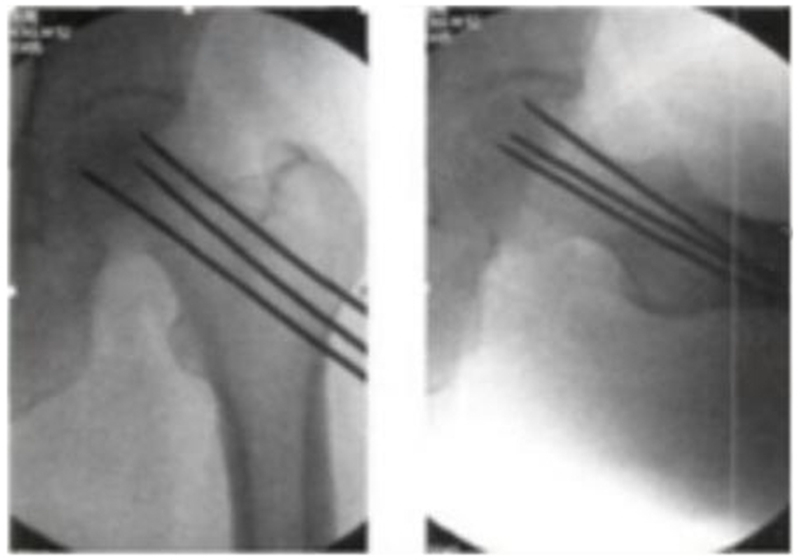

3、多孔细(Multiple CD,MCD)髓芯减压术

为了克服单孔髓芯减压术的缺点,科学家们进行了改进,采用细针进行多孔道的髓芯减压,通过以直径为3-4mm的克氏针代替传统钻头,进行多方向多孔道的减压MCD和SCD相比,可到达更多的坏死区域,减压更彻底,手术创伤更小。由于对股骨头、股骨颈处结构影响小,保留孔道之间的支撑结构,因此股骨头塌陷、骨折等并发症发生率也更低。

2004年,Mont首次报道多孔径技术对股骨头坏死塌陷前FicatⅠ期患者2年随访,其成功率为80%。2008年,David研究表明,多孔径髓芯减压术组较传统髓芯减压术组,可适应坏死分期更高。文献报道在坏死范围较小者,失败率在14%-25%,坏死范围较大者,失败率达42%-84%。

2016年Brown也认为,经皮多孔径随芯减压术(MCD)较传统单孔芯减压术(SCD),有更少软骨损害及转子下骨折及容易操作等优势,但临床疗效相近,不管是SCD还是MCD,在减压后股骨头修复的过程中,骨吸收的速度往往较新骨的形成快,使本薄弱的软骨下骨的机械支撑力进一步减弱从而更易引起股骨头塌陷,塌陷率仍有30%左右,患者仍需拄拐下地或限制活动。

优点:①手术操作相对简单,容易实施;②创伤小,对组织破坏较少;③手术无效或失败不影响其它手术的实施。